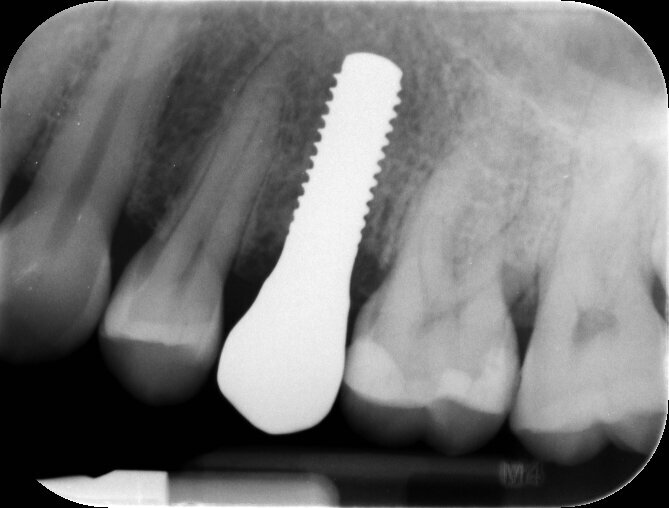

In questo caso dato il mutuo contatto tra osso e impianto non è stato necessario alcun riempimento e seppur altamente stabile, il provvisorio è stato rimosso dal contatto masticatorio e da eventuali svincoli funzionali. Al termine del posizionamento eseguiamo un controllo radiografico che stabilisce il giorno zero d’inserimento, la valutazione globale di posizione e un controllo di eventuali residui cementizi presenti (Fig. 5). Dopo un periodo di consolidamento osseo di 3 mesi si procede al processo di finalizzazione protesica. Il condizionamento dei tessuti molli ottenuto dal provvisorio favorisce la futura realizzazione protesica fornendo un aspetto naturale simile al dente naturale precedente (Fig. 6).

Fig. 5_Rx di controllo post operatoria con provvisorio in situ, serve per stabilire la posizione dell’impianto in tempo post chirurgico e per valutare se vi è del residuo cementizio al di sotto della corona provvisoria.